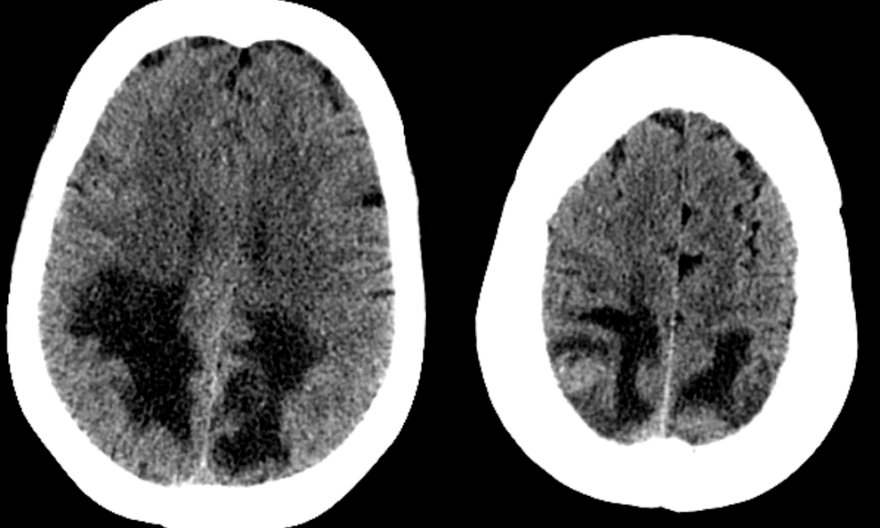

Case history: 55 year old female with history of lung adenocarcinoma presents with difficulty seeing. She was treated with carboplatin and paclitaxil two months prior to admission. CT head showed hypodensities in bilateral posterior white matter, as shown below. What is your diagnosis?

Initial interpretation based on posterior hypodensity was like PRES (Posterior Reversible Encephalopathy Syndrome) especially given recent paclitaxel and carboplatin use (both of which have been associated with PRES). Subsequent MRI with and without contrast, however, showed multiple enhancing lesions, suggesting metastatic disease without PRES.